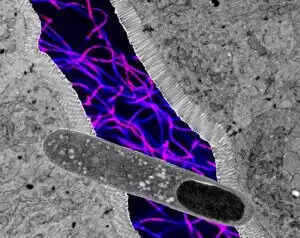

चूहों पर की गई स्टडी में, यूटा यूनिवर्सिटी की टीम ने पाया कि खास तरह का गट बैक्टीरिया 'ट्यूरिसीबैक्टर' मेटाबॉलिक हेल्थ को बेहतर बनाने में सक्षम है और वजन को बढ़ने न देने में भी कारगर है।

ट्यूरिसीबैक्टर, एक रॉड के आकार का बैक्टीरिया है जो हाई-फैट डाइट वाले चूहों में ब्लड शुगर, खून में फैट का लेवल और वजन बढ़ने को अकेले ही कम करता पाया गया।

रिसर्चर्स ने पाया कि ट्यूरिसीबैक्टर, सेरामाइड्स नामक फैटी मॉलिक्यूल बनाने के तरीके को प्रभावित करके मेटाबॉलिक हेल्थ को बेहतर बनाता है।